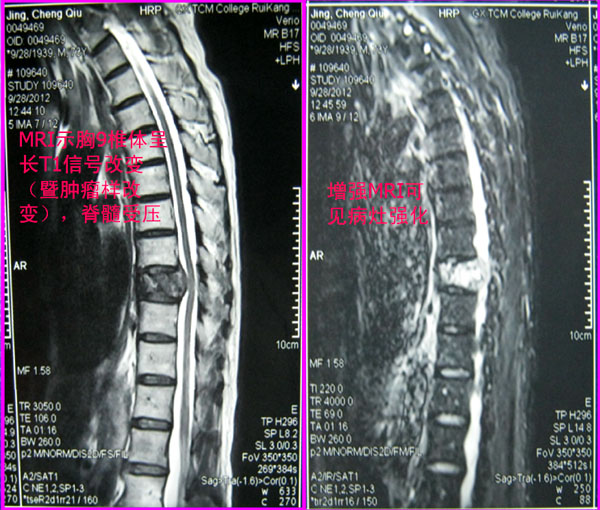

该男性患者现年73岁,自述其反复胸背部疼痛约8个多月,病情加重1周后入院。瑞康医院骨脊柱科专家为其检查身体发现,其胸背部有压痛、叩击痛。患者的胸椎X光片显示其胸9椎体有病理性压缩骨折(图1),胸椎CT片显示其椎体破坏(图2),胸椎MRI检查显示其胸9椎体及椎弓呈现长T1异常信号改变(即肿瘤样改变),椎体后缘突入椎管,导致脊髓受压,增强MRI可见病灶强化影(图3)。前列腺MRI提示该患者患前列腺癌的可能性较大。

胸椎MRI检查示胸9椎体及椎弓呈长T1异常信号改变,椎体后缘突入椎管,脊髓受压,增强MRI可见病灶强化影